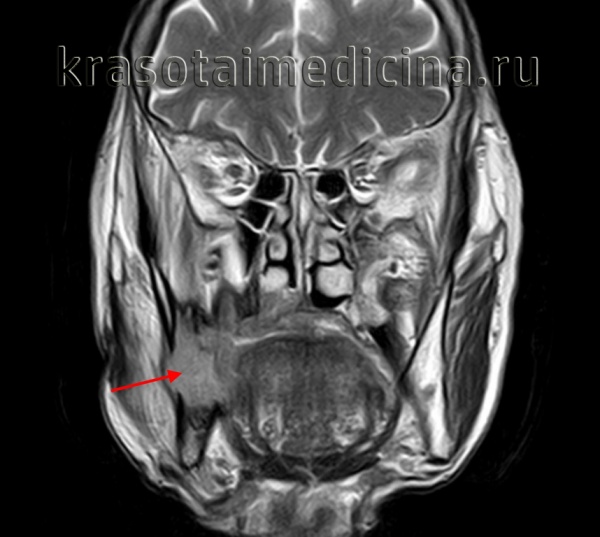

(Слева) На панорамной реформатированной КЛКТ определяется крупная АФ в задних отделах нижней челюсти, связанная с коронкой формирующеюся непрорезавшегося второго постоянного моляра АФ, содержащая перегородки, выбухает в задние отделы ветви.

(Справа) На трехмерной реконструкции (вид спереди) у этого же пациента визуализируются корни постоянного первого моляра нижней челюсти слева в АФ.

(Слева) На КЛКТ (вид сбоку) у этою же пациента определяется поражение венечного отростка. Обратите внимание на тонкую перегородку в образовании.

(Справа) На трехмерной реконструкции (КЛКТ) у этого же пациента визуализируется АФ (вид снизу). Обратите внимание на вздутие щечной кортикальной пластинки в образовании отчетливо видны мезиальный и дистальный корень первою моляра. Нижний край нижней челюсти сохранен.

(Слева) На аксиальной КЛКТ у этого же пациента визуализируется АФ. Кортикальная пластинка вздута и истончена, но не перфорирована. Обратите внимание, что края опухоли соединяются с нормальной кортикальной пластинкой под острым углом, что характерно для опухоли, но не для кисты, приводящей к гидравлической экспансии и переходящей в кортикальную пластинку под более тупыми углами.

(Справа) На корональной КЛКТ у этого же пациента определяется АФ, приводящая к вздутию преимущественно щечной кортикальной пластинки.